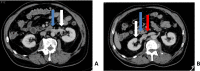

Duplication of the inferior vena cava is a rare malformation, normally without clinical impact, explained by abnormal development and regression of certain segments of the venous system during embryonic life. However, its presence and type should be systematically reported in the radiological report because of its potential implications for diagnostic and interventional procedures. This observation describes the case of a 77-year-old man with a complete asymmetric duplication of the inferior vena cava (type III IVC according to Natsis) that was incidentally discovered on CT-scan.